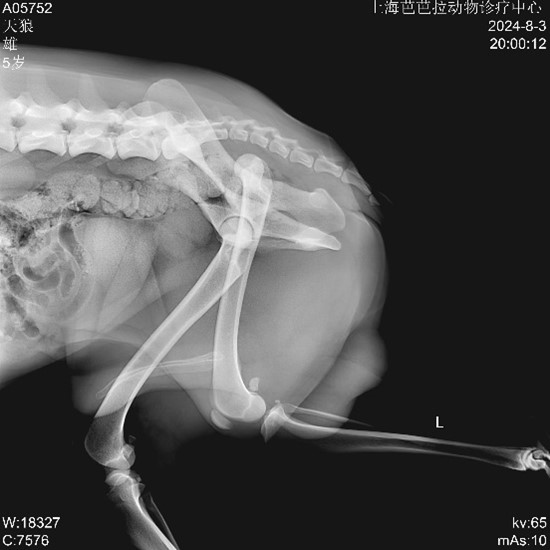

▼ Pre-op Imaging

▲ Diagnosis: Left femoral head luxation